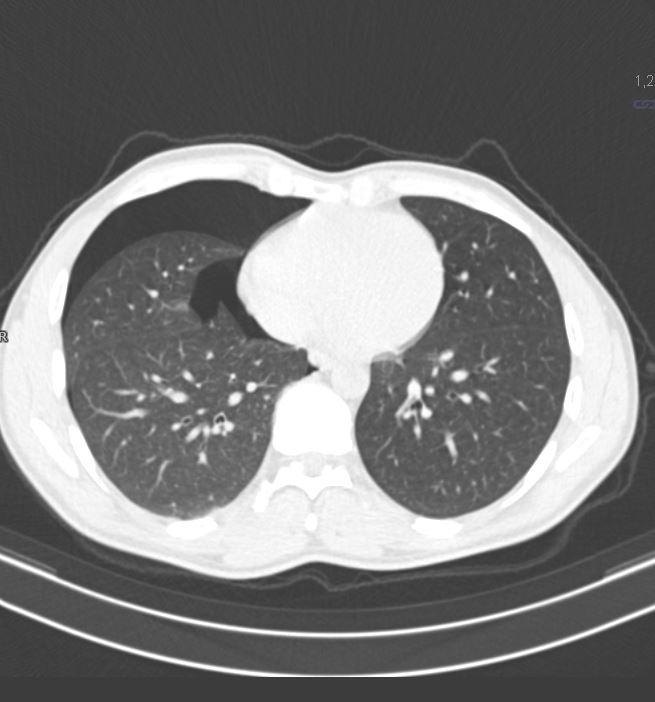

*27-year-old male with pleuritic chest pain and mild dyspnoea.

What is the most likely diagnosis?

Answer: Secondary spontaneous pneumothorax secondary to blebs